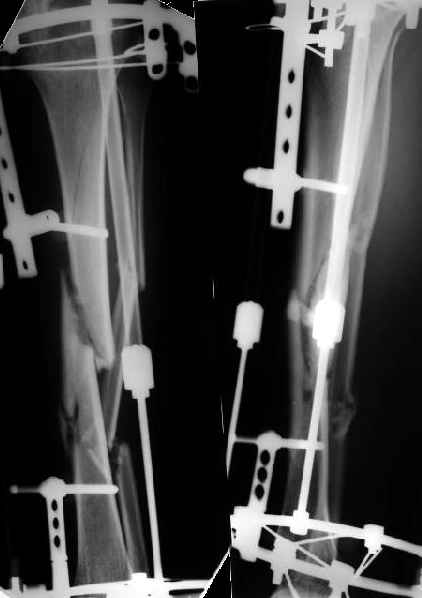

Как я уже сообщал, пациент поступил к нам в пятницу на прошлой неделе.

Сегодня сделана операция. Из бедра минимально инвазивно удалены пластинки. Один винт на верхней пластинке оказался сломан, так что пришлось там сделать разрезик побольше, см 5.

Хотя и с трудом, но на бедре удалось сразу выполнить закрытый интрамедуллярный остеосинтез с минимальным рассверливанием.

На голени - чрескожная остеотомия малоберцовой кости, закрытая остеоклазия большеберцовой, дистракционный остеосинтез аппаратом.

В плане - востановление длины и оси голени, разработка движеий в колене. Не уверен, что удастся синтезировать голень стержнем при таком маленьком сгибании в коленном суставе.